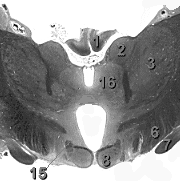

На поперечных срезах среднего мозга видно, что в толще холмиков крыши среднего мозга (colliuli tecti mesencephali) залегают скопления серого вещества, в верхнем холмике (colliculus superior) они называются серым слоем верхнего холмика (stratum griseum colliculi superioris), а в нижнем (colliculus inferior) – ядром нижнего холмика (nucleus colliculi inferioris). Серый слой верхнего холмика состоит из зрительных ядер, а ядро нижнего холмика – из слуховых.

Медиальнее расположен мозговой водопровод (aquaeductus cerebli), вокруг которого располагается центральное серое вещество (sub>stantia grisea centralis). В его толще залегают ядра глазодвигательного и блокового нервов (nuclei nervi oculomotorius et trochlearis).

Вентральнее можно различить большие красные ядра (nuclei ruber) и черное вещество (sub>stantia nigra). Эти структуры относятся к двигательной системе.

Рис. Поперечный срез среднего мозга на уровне верхнего холмика.

1. sub>stantia grisea centralis

2. Aqueductus cerebri

4. Pedunculus cerebri

5. Nucleus rubber

6. sub>stantia nigra

7. Fossa interpeduncularis

9. Colliculus superior